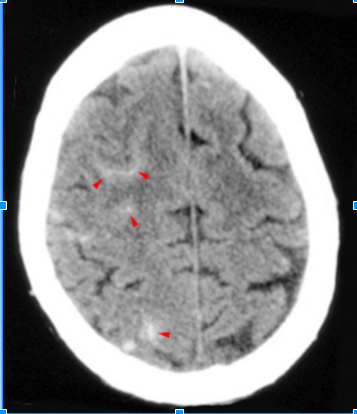

- SAH: What is the injury to?

- Where do the ruptured vessels bleed?

- Injury of small arteries or veins on the surface of the brain

- Ruptured vessel bleeds into the space between the pia and arachnoid mater

Causes of subarachnoid hemorrhage

2

(most common)?

- Trauma

Most common cause

- Ruptured cerebral aneurysm

What (arrowheads) fills the sulci over the

right cerebral convexity in this subarachnoid hemorrhage?

See Picture

High density blood